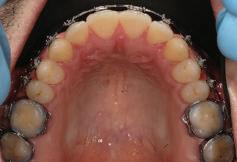

Dental Tribune Bulgarian Edition / октомври 2022 г.18 воначалния план. Тези пробле ми бяха адресирани чрез допъл нителна поръчка на алайнери с торк контрол и зададено екст рудиране на задните зъби с цел установяване на добри оклузал ни контакти в дисталните об ласти, като бяха предвидени и оптимизирани атачмънти с контрол над корените за корекция на ангулацията на макси ларните резци (фиг. 8). Резултати от лечението Панорамната рентгено графия след ортодонтското лечение показа благоприятна паралелна позиция на съседни те зъби, подходяща за поставя не на имплант в областта на #22, както и конвергенция на ко рените на зъби #44 и 45 (фиг. 9), но преценихме, че няма да от деляме допълнително лечебно време за коригирането ѝ поради факта, че пациентката бе мно го доволна от постигнатия до момента резултат. След при ключване на лечението бяха постигнати отлични взаимо отношения клас I при мола рите и канините, а срединни

съвпадаха. Върху им

ти и клас II ластици е устано вено, че осигурява достатъч на дистализация без промяна на лицевата височина.23 Както се видя от цефалометричния анализ, точно това бе постиг нато и в представения случай като се има предвид, че лице вата височина остана същата като първоначалната. Предвид леката тенденция към дистал Фиг. 8a–e Поръчаните допълнителни алайнери. Фиг. 9 Панорамна рентгенография след края на лечението. Фиг. 10a–c Странични (а и с) и фронтална интраорални снимки след края на ортодонтското лечение и поставянето на импланта (b). Зъб #12 все още не беше протезиран. Фиг. 11а и b Оклузални снимки след ортодонтското лечение. Фиг. 7a Фиг. 8a Фиг. 7d Фиг. 8d Фиг. 9 Фиг. 10a Фиг. 10b Фиг. 10c Фиг. 11bФиг. 11a Фиг. 7b Фиг. 8b Фиг. 7e Фиг. 8e Фиг. 7c Фиг. 8c Фиг. 7a–e Интраоралната ситуация по време на лечението. клиничен случай с алайнери

Dental Tribune Bulgarian Edition / октомври 2022 г. 19 на отворена захапка е устано вено, че финалното адаптиране и подобряване на оклузалните контакти се установяват след повече от три месеца след лече нието.24 Следователно подобря ване на ситуацията и плътни оклузални контакти се очак ват след края на лечението. Що се отнася до избора за замест ване на липсващия латерален резец с единичен имплант и протезирането му, установе но е, че това е най-често при лаганата лечебна алтернати ва.25 Съседните зъби остават интактни и следователно най голямото предимство на този подход е съхраняването на здра ви зъбни структури. Изборът ни на лечебен план бе базиран на детайлна мул тидисциплинарна диагноза и планиране, а те категорично са ключови за постигане на оп тимални индивидуални резул тати при пациенти

но

между членовете на екипа и пациента. ЗАКЛЮЧЕНИЕ Случаите на липсващи лате рални резци трябва да бъдат третирани от перспектива та на интердисциплинарна ди агностика и лечение. Употреба та на софтуера ClinCheck има доказани предимства за плани ране, комуникация между кли ницистите и пациента и фи нализиране на лечебния план, като се адресират всички же лания и притеснения на паци ента. Настоящият доклад на клиничен случай доказва, че с помощта на съвременните ме тоди един успешен екип от спе циалисти (ортодонт, консерва тивен зъболекар и хирург) може да се стреми към отлични ре зултати и да постига есте тични и функционални усмив ки без компромиси. Ред. бел.: Статията Treatment of a patient with a congenitally missing lateral incisor using aligners: A case report е пуб ликувана за първи път в сп. aligners–international magazine of aligner orthodontics, бр. 1, издание 1/2022. Библиографията е налична при издателя. За авторите: Д-р Iro Eleftheriadi завършва дентална медицина в Атинския университет, а магистратурата си по медицинска статистика – през 2014 г. в Публичния университет в Атина, Гърция. Специализира ортодонтия и завършва през 2017 г. в Университета в Тел Авив, Израел. Предстои ѝ да защити докторан тура във Факултета по дентална медицина към Университета в Атина, Гърция. Д-р Christodoulos Laspos завършва дентална медицина през 1995 г. в Атинския университет, Гърция, а магистратурата си завършва през 1999 г. във Фа култета по дентална медицина към Университета в Тенеси, Мемфис, САЩ. Печели стипендия и специализира лечение на пациенти с лицево-челюстни малформации в Университета в Тексас, Далас, САЩ, и е сертифициран специалист от Европейския борд на ортодонтите. Той е докторант в Универ ситета в Берн, Швейцария. От 2000 г. д-р Laspos практикува в частната си ортодонтска практика в Лимасол, Кипър. Той е основател и директор на MEDICLEFT, Кипърски център за цепки и лицево-челюстни аномалии, както и директор на фондацията Synergy, която осигурява следдипломно обучение на лекари по дентална медицина. Научен съ трудник е във Факултета по дентална медицина към Европейския университет в Кипър. Д-р Laspos изнася лекции по цял свят по теми като лицево-челюстни мал формации, ортогнатна хирургия, мултидисциплинарен подход и нови технологии в ортодонтията. Той е активен член на Европейското общество на Енгел и прези дент на Европейското ортодонтско общество. Фиг. 12а–c Финални странични (а и c) и фронтална интраорални снимки (b). Фиг. 13а и b Финални оклузални снимки. Фиг. 14 Финална снимка на усмивката отблизо. Фиг. 15 Финална екстраорална снимка на усмивката. Фиг. 16 Финална телерентгенография и цефалометричен анализ. Фиг. 12a Фиг. 13a Фиг. 14 Фиг. 15 Фиг. 16 Фиг. 13b Фиг. 12b Фиг. 12c клиничен случай с алайнери